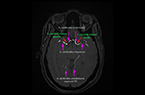

Cerveau de femme adulte - Réseau vasculaire artériel - Principales artères cérébrales et leurs parcours Cerveau de femme adulte - Réseau vasculaire artériel - Principales artères cérébrales et leurs parcours Cerveau de femme adulte - Réseau vasculaire artériel - Principales artères cérébrales et leurs parcours